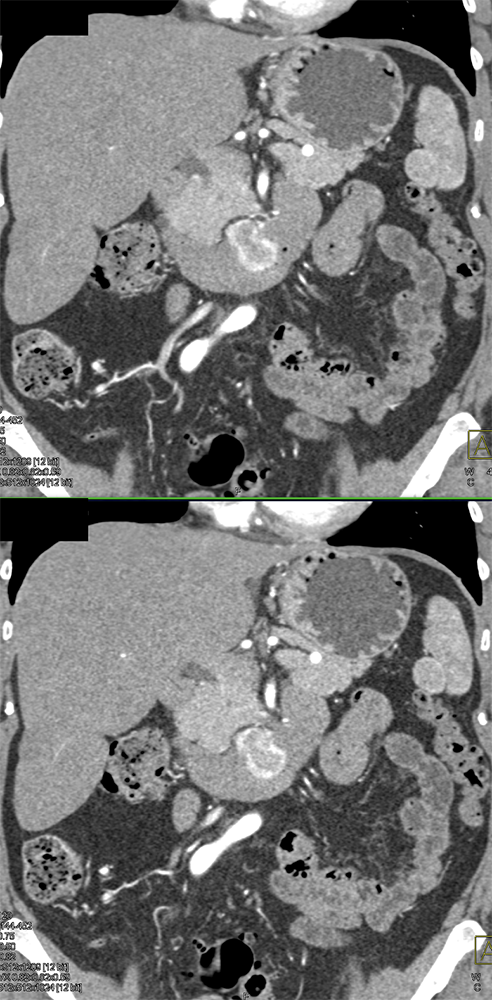

RCC Metastatic to Small Bowel ![]() |

![]() |